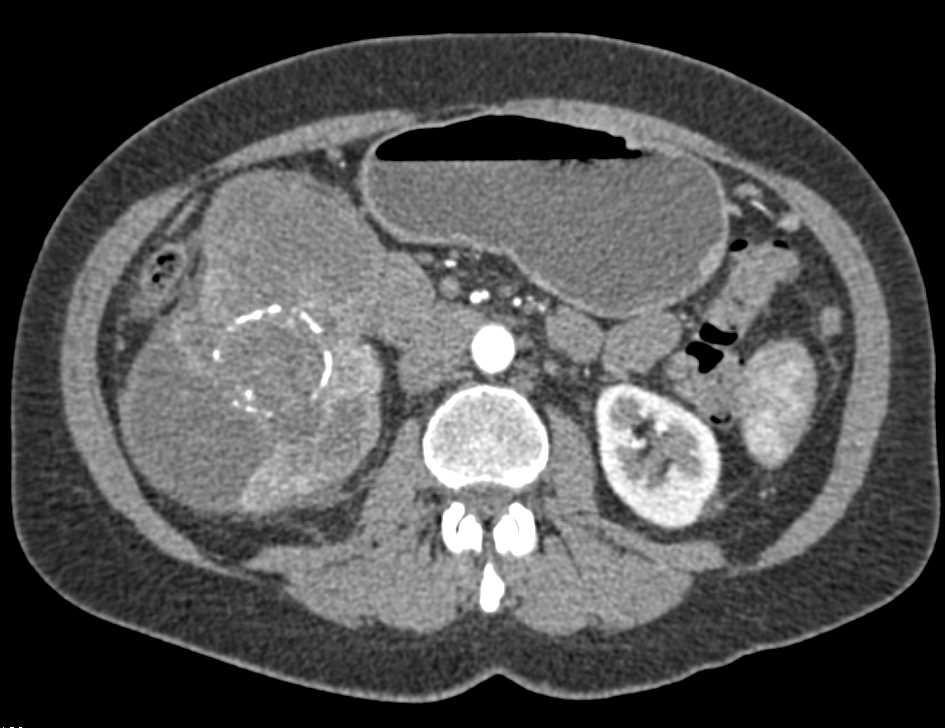

Incidental Left Renal Cell Carcinoma in Patient with a Pseudocyst